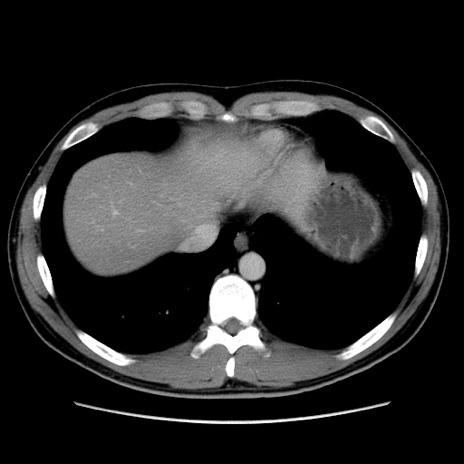

症例36(横断像)

冠状断像

【症例】20歳代 男性

【主訴】心窩部痛

【現病歴】今朝より上腹部痛あり。一旦軽快していたが再度出現したため救急要請。昨日夕に白身の魚を含む刺身を食べた。

【身体所見】BP 136/89mmHg、HR 74/min、BT 37.0℃、腹部:膨満、軟、心窩部に圧痛あり。反跳痛なし、筋性防御なし、腸雑音やや亢進あり。

【データ】WBC 17700、CRP 0.48